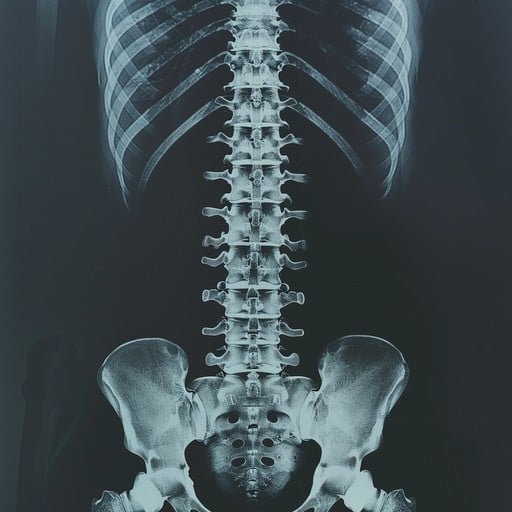

脊髄損傷による麻痺に新たな光:3Dプリンターと幹細胞で神経回路を再建 一度損傷すると完全な回復は難しいとされる脊髄。この大きな課題に対し、3Dプリンター、幹細胞生物学、そして研究室で培養した組織を組み合わせた画期的なプロセスによって、脊髄損傷からの回復を実証した研究が登場しました。 ミネソタ大学ツインシティーズ校の研究チームが開発したこの新技術は、損傷した神経が再生するための「架け橋」となり、麻痺治療に新たな希望をもたらす可能性があります。この研究は、2025年7月23日に査読付き科学雑誌「Advanced Healthcare Materials」に掲載されました。論文のタイトルは「3D-Printed Scaffolds Promote Enhanced Spinal Organoid Formation for Use in Spinal Cord Injury(3Dプリントされた足場は脊髄損傷で使用するための脊髄オルガノイド形成を促進する)」です。 米国立脊髄損傷統計センターによると、米国では30万人以上が脊髄損傷に苦しんでいますが、損傷によるダメージやまひを完全に元に戻す方法は確立されていません。大きな課題は、神経細胞が死んでしまうこと、そして神経線維が損傷部位を越えて再生できないことにあります。今回の新しい研究は、この問題に正面から取り組むものです。 この方法は、研究室で培養したミニ臓器であるオルガノイドのための、微細なチャネル(流路)を持つユニークな3Dプリントされたフレームワーク、「オルガノイド足場」を作製することから始まります。これらのチャネルには、ヒトの成人幹細胞から作られ、特定の種類の成熟細胞に分裂・分化する能力を持つ「脊髄神経前駆細胞(sNPCs: spinal neural progenitor cells)」が配置されます。 「私た